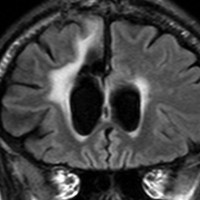

乳児の髄芽腫の治療後の硬膜血管腫

生後8ヶ月で髄芽腫を発症して,手術後に8コースの化学療法して,残存腫瘍があったために2歳半で脳脊髄照射18グレイと後頭窩局所照射21.6グレイをしました。放射線治療後2年で見つかった左前頭部腫瘍です。てっきり脳表播種再発かと思いましたが,良性の硬膜血管腫でした。この子は20歳となり再発もなく元気です。幼児期の放射線治療あるいは化学療法は,予想より早期に,珍しい2次腫瘍を誘発することがあると考えたほうがいいのでしょう。この腫瘍の部位には1日線量1.8グレイで18グレイしか照射されていませんでした。